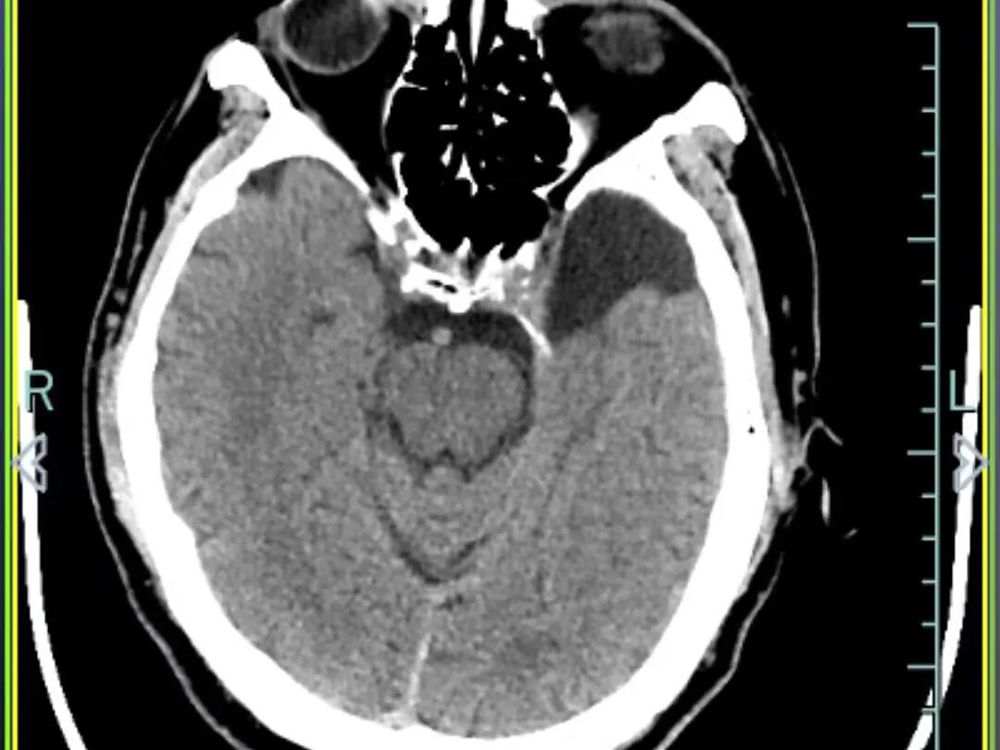

医院快速开通绿色通道并完善一系列检查后,诊断结果令人揪心:孙先生患有重型闭合性颅脑损伤,包括多发性创伤性脑出血、右侧颞部创伤性硬膜下出血、创伤性蛛网膜下腔出血以及脑震荡,同时合并多处骨折及软组织挫裂伤。

硬膜下出血、蛛网膜下腔出血和多发性创伤性脑出血